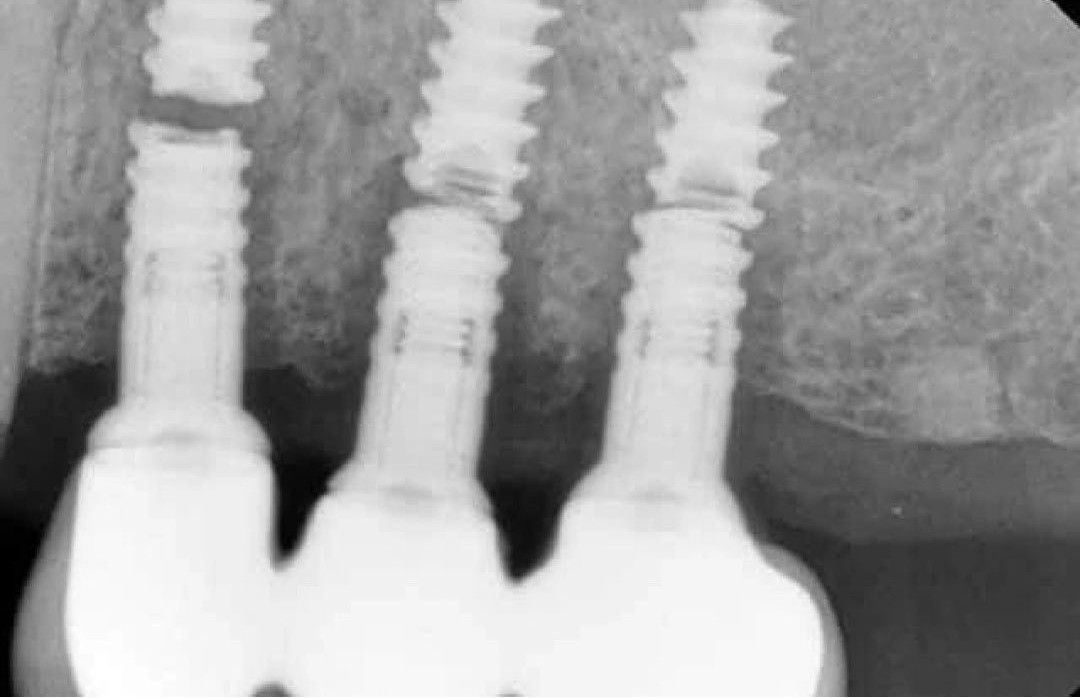

Implant Fracture

What could be the causes of dental implant fracture?